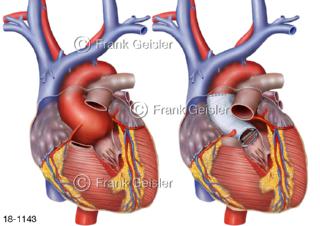

18-1143 Erkrankung Aorta Herz, Aneurysma Aortenklappe Sinusportion Sinus aortae Valsalvae